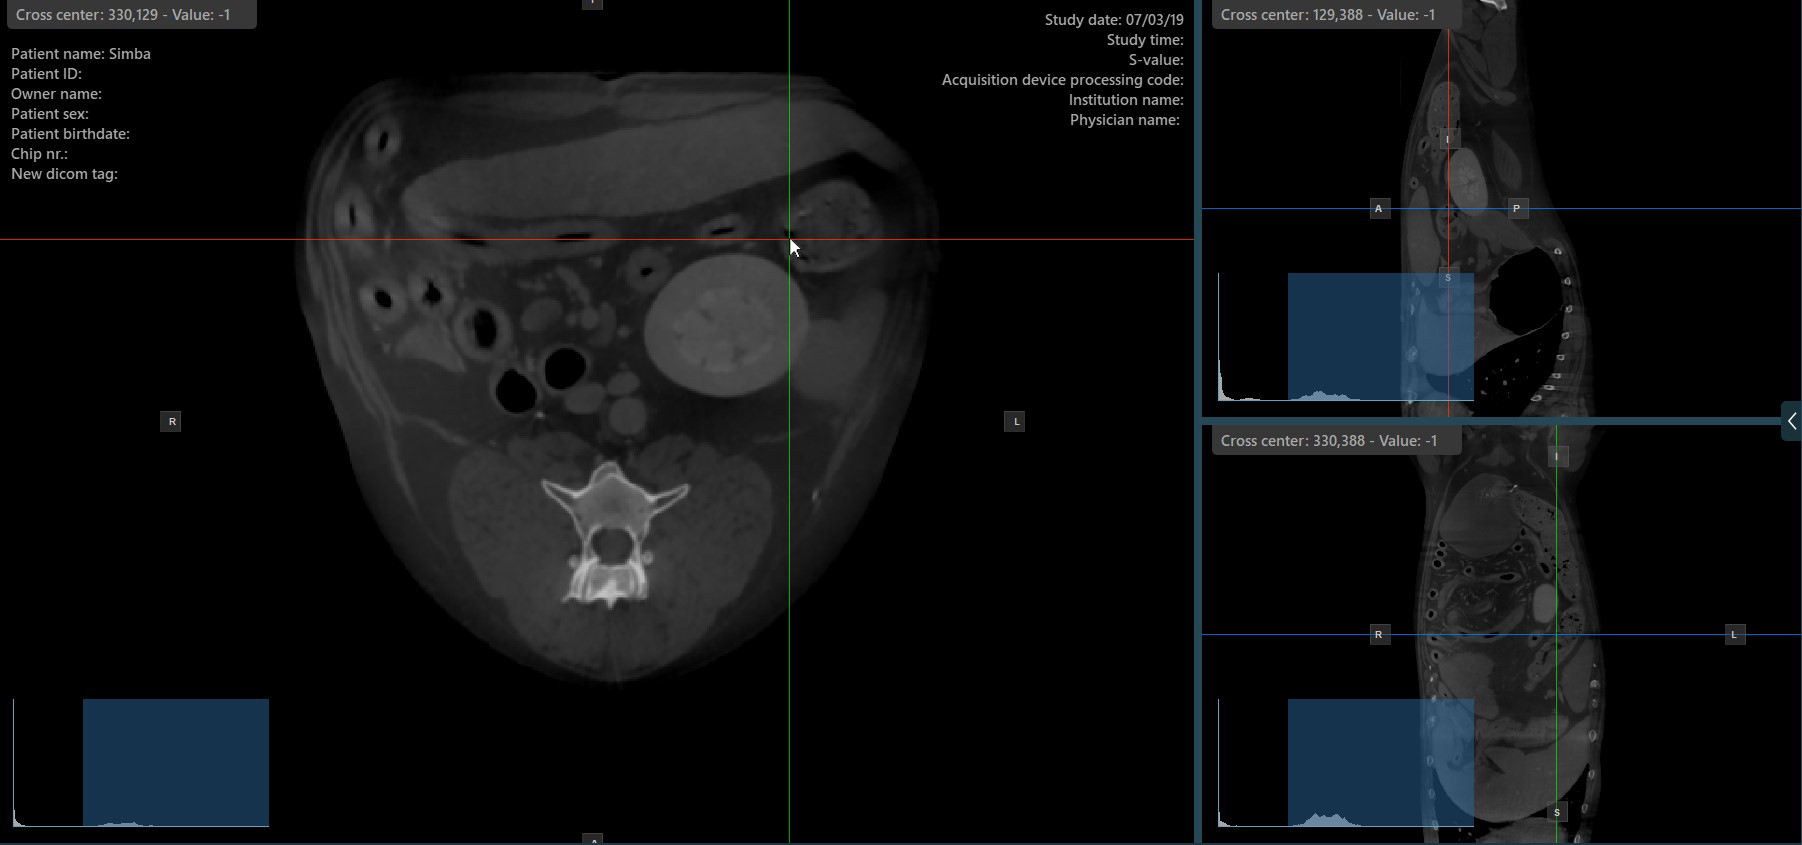

By default, each slicer can be rotated separately. The corresponding icon in the left toolbar of the CT Viewer will be deselected when the slicers are rotated individually.

Press the Perpendicular Slicers icon in the left toolbar to activate simultaneous rotation of the slicers. Regardless of their previous orientation, the slicers are repositioned to be perpendicular to each other.